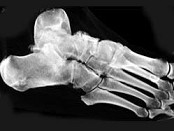

- 单项选择题男,56岁, 踝关节肿胀,有糖尿病史, 结合图像,最可能的诊断是 ( )

A、创伤性关节炎

B、退行性关节病

C、痛风

D、类风湿关节炎

E、神经性关节病